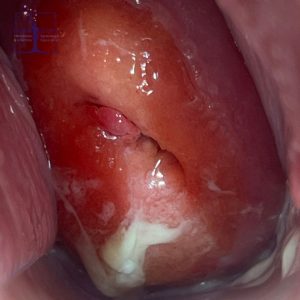

تست پاپ اسمیر چیست و چگونه انجام می شود؟

چه کسانی باید آزمایش پاپ اسمیر بدهند؟ به طور کلی